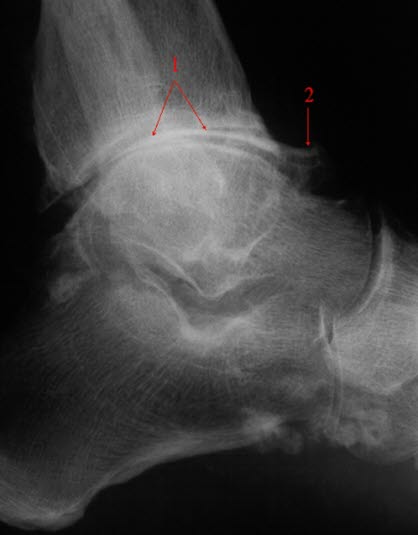

Ankelartrose, skrå frontSkade eller sykdom i leddet disponerer for utvikling av artrose. Dette kan for eksempel være ankelbrudd eller kraftig overtråkk som ikke er tilstrekkelig tilhelet. Overvekt disponerer også for artrose. Ellers vil arbeid eller aktivitet som innebærer store belastninger på bena gjennom et langt liv, være en viktig disponerende faktor.

Forkalkninger og redusert leddspalte.Plagene er typiske. Kombinert med vanlig legeundersøkelse av ankelen kan diagnosen være sannsynlig uten andre undersøkelser. Sikker diagnose fås ved røntgenundersøkelse som viser nedslitt brusk og eventuelt forandringer i selve beinstrukturen.